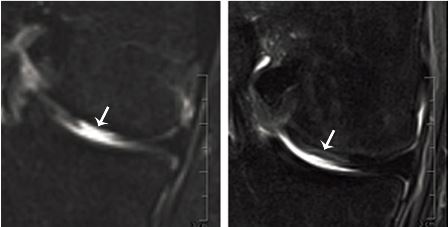

MRI of defect tissue site before (left) and four months after (right) transplantation

Articular cartilage replaced: MRI of defect tissue site before (left) and four months after (right) transplantation (Fig: Department of Biomedicine, University of Basel)